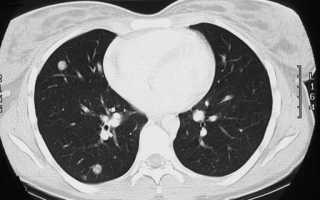

Определение пути и характера метастазов можно по результатам компьютерной томографии, благодаря исследованию, определяют первичный очаг злокачественной опухоли. Обычно метастазы в легких – это рак 4 стадии.

- компьютерная томография – современный и доступный метод определения вторичных раковых очагов, расположенных глубоко в тканях плевры;